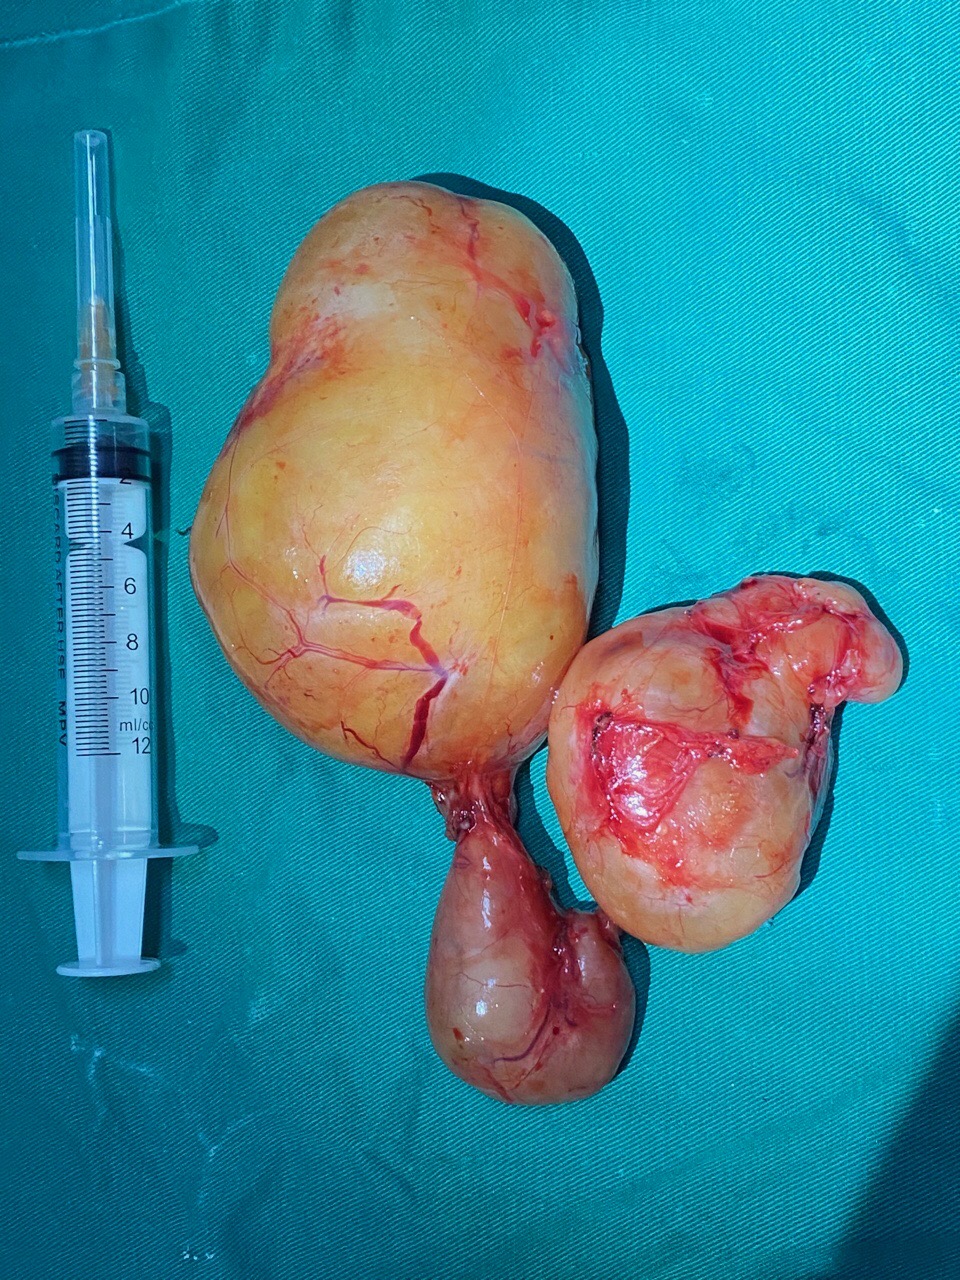

Xác định đây là một ca bệnh khó, hiếm gặp do khối u nằm ở vị trí khó và có kích thước lớn, các Bác sĩ đã tiến hành hội chẩn liên chuyên khoa gồm các chuyên khoa Ngoại Tiết niệu, Hồi sức tích cực 2, Phẫu thuật TKLN, Gây mê hồi sức. Sau hội chẩn, các Bác sĩ quyết định phẫu thuật mở cắt bỏ khối u cho bệnh nhân. Kíp phẫu thuật gồm Ts.Bs Trương Thanh Tùng (Trưởng phòng KHTH – Phó trưởng khoa Ngoại Tiết niệu), Bs Lê Đức Thành (Khoa HSTC 2), Bs Mai Thành Thắng (Khoa PTTK-LN) và kíp gây mê gồm Bác sĩ Lê Ngọc Sơn, KTV Đại, Nhung, Duyên (khoa GMHS). Bệnh nhân được gây mê đặt nội khí quản và được theo dõi huyết áp động mạch. Do có sự chuẩn bị chu đáo về nhân lực, trang thiết bị và sự phối hợp của tất cả các ê-kíp, ca mổ đã diễn ra thành công tốt đẹp. Sau hơn 2 giờ phẫu thuật, khối u được bóc và lấy ra nguyên vẹn, không bị xâm lấn hoặc tổn thương các tạng xung quanh, bệnh nhân không phải truyền máu.

Hình ảnh khối u sau khi được phẫu thuật